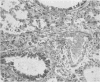

The pathological lesions attributable to paraquat are described in some detail. Among the most unusual is a peculiar proliferative condition in the lungs, which in an extreme case and in many parts can hardly be recognized as consisting of pulmonary tissue. With slight variations, the same microscopical picture may be seen in the rat, mouse, dog, and man, and less often in the rabbit. The experimental evidence suggests that once the condition is initiated it often proceeds in the absence of further exposure to paraquat until it becomes lethal.